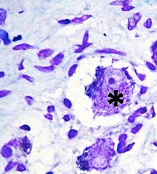

TIPO DE NEURONA SEÑALADA CON EL ASTERISCO EN LA IMAGEN.

Respuesta escrita

ESTAS NEURONAS SUELEN TENER UN SOMA DE SUPERICIE IRREGULAR YA QUE CORRESPONDE A DENDRITAS QUE SE ORIENTAN EN DIFERENTES DIRECCIONES.